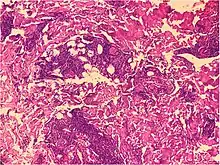

| Prevesicular stage of bullous pemphigoid | Image at right shows influx of inflammatory cells including eosinophils and neutrophils in the dermis (solid arrow) and blister cavity (dashed arrows), and deposition of fibrin (asterisks).[15] However, the diagnosis of bullous pemphigoid consist of at least 2 positive results out of 3 criteria:[19]

|

|

|